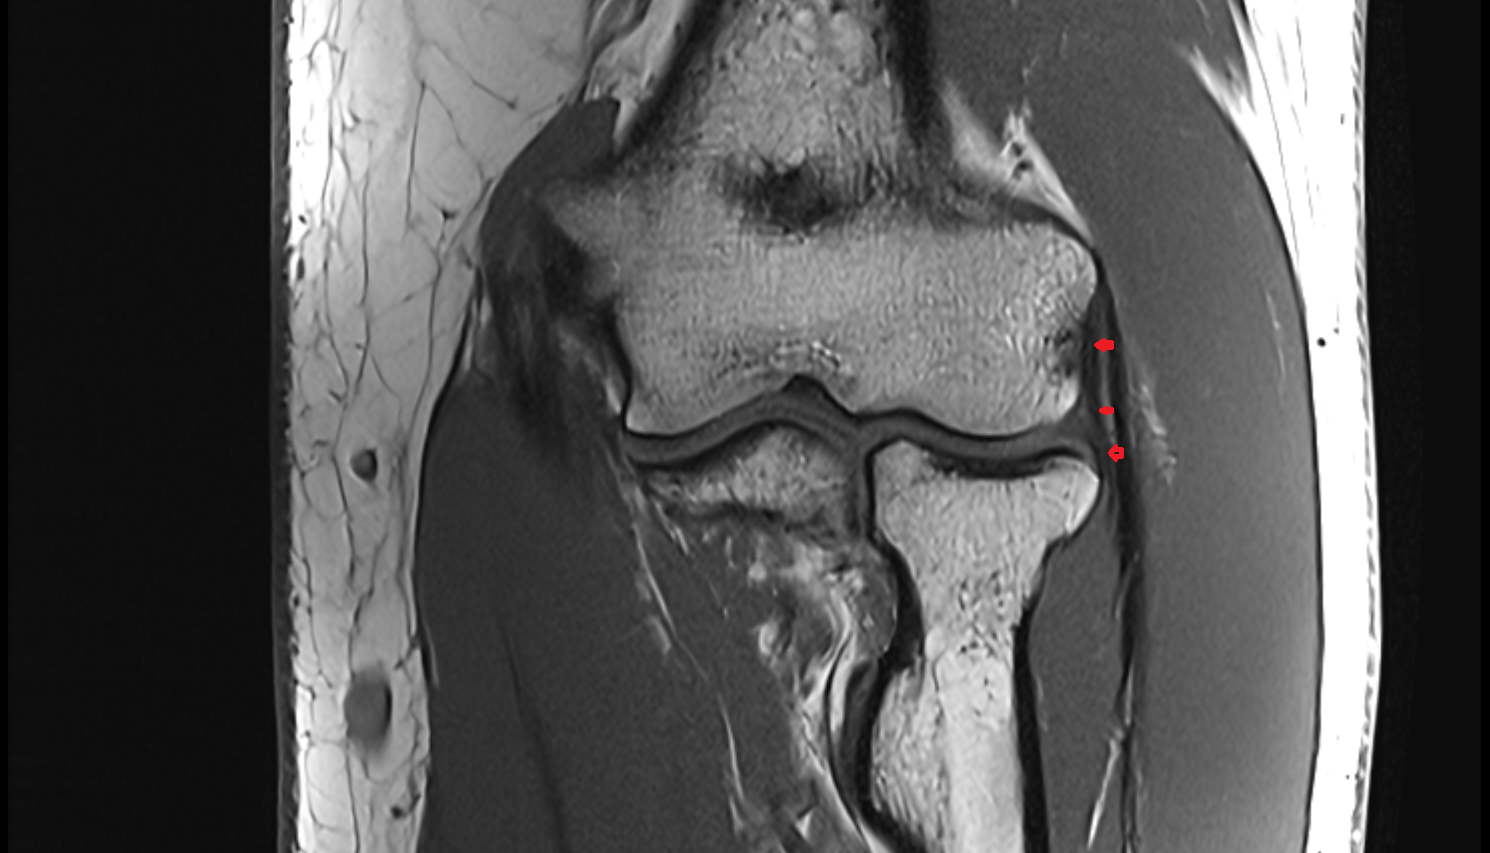

- Medial collateral ligament